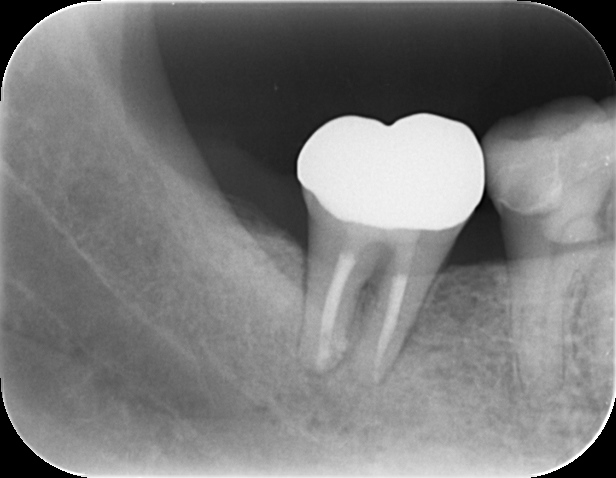

できものの出口からレントゲンに写るゴムを挿入して写真を撮ると、根の先で渦を巻いており、ここに膿の袋ができていることがわかります。

治療前のレントゲンで根の先が黒く写っています。これは歯の中の神経が壊死してしまい感染を起こしています。